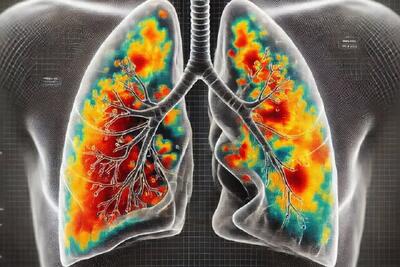

هوش مصنوعی بیماری های ریوی را با دقت بالایی تشخیص می دهد

یک تیم تحقیقاتی در استرالیا موفق به توسعه یک مدل هوش مصنوعی با قابلیت تشخیص بیماریهای ریوی از جمله ذاتالریه با دقت فوقالعاده شدهاند.